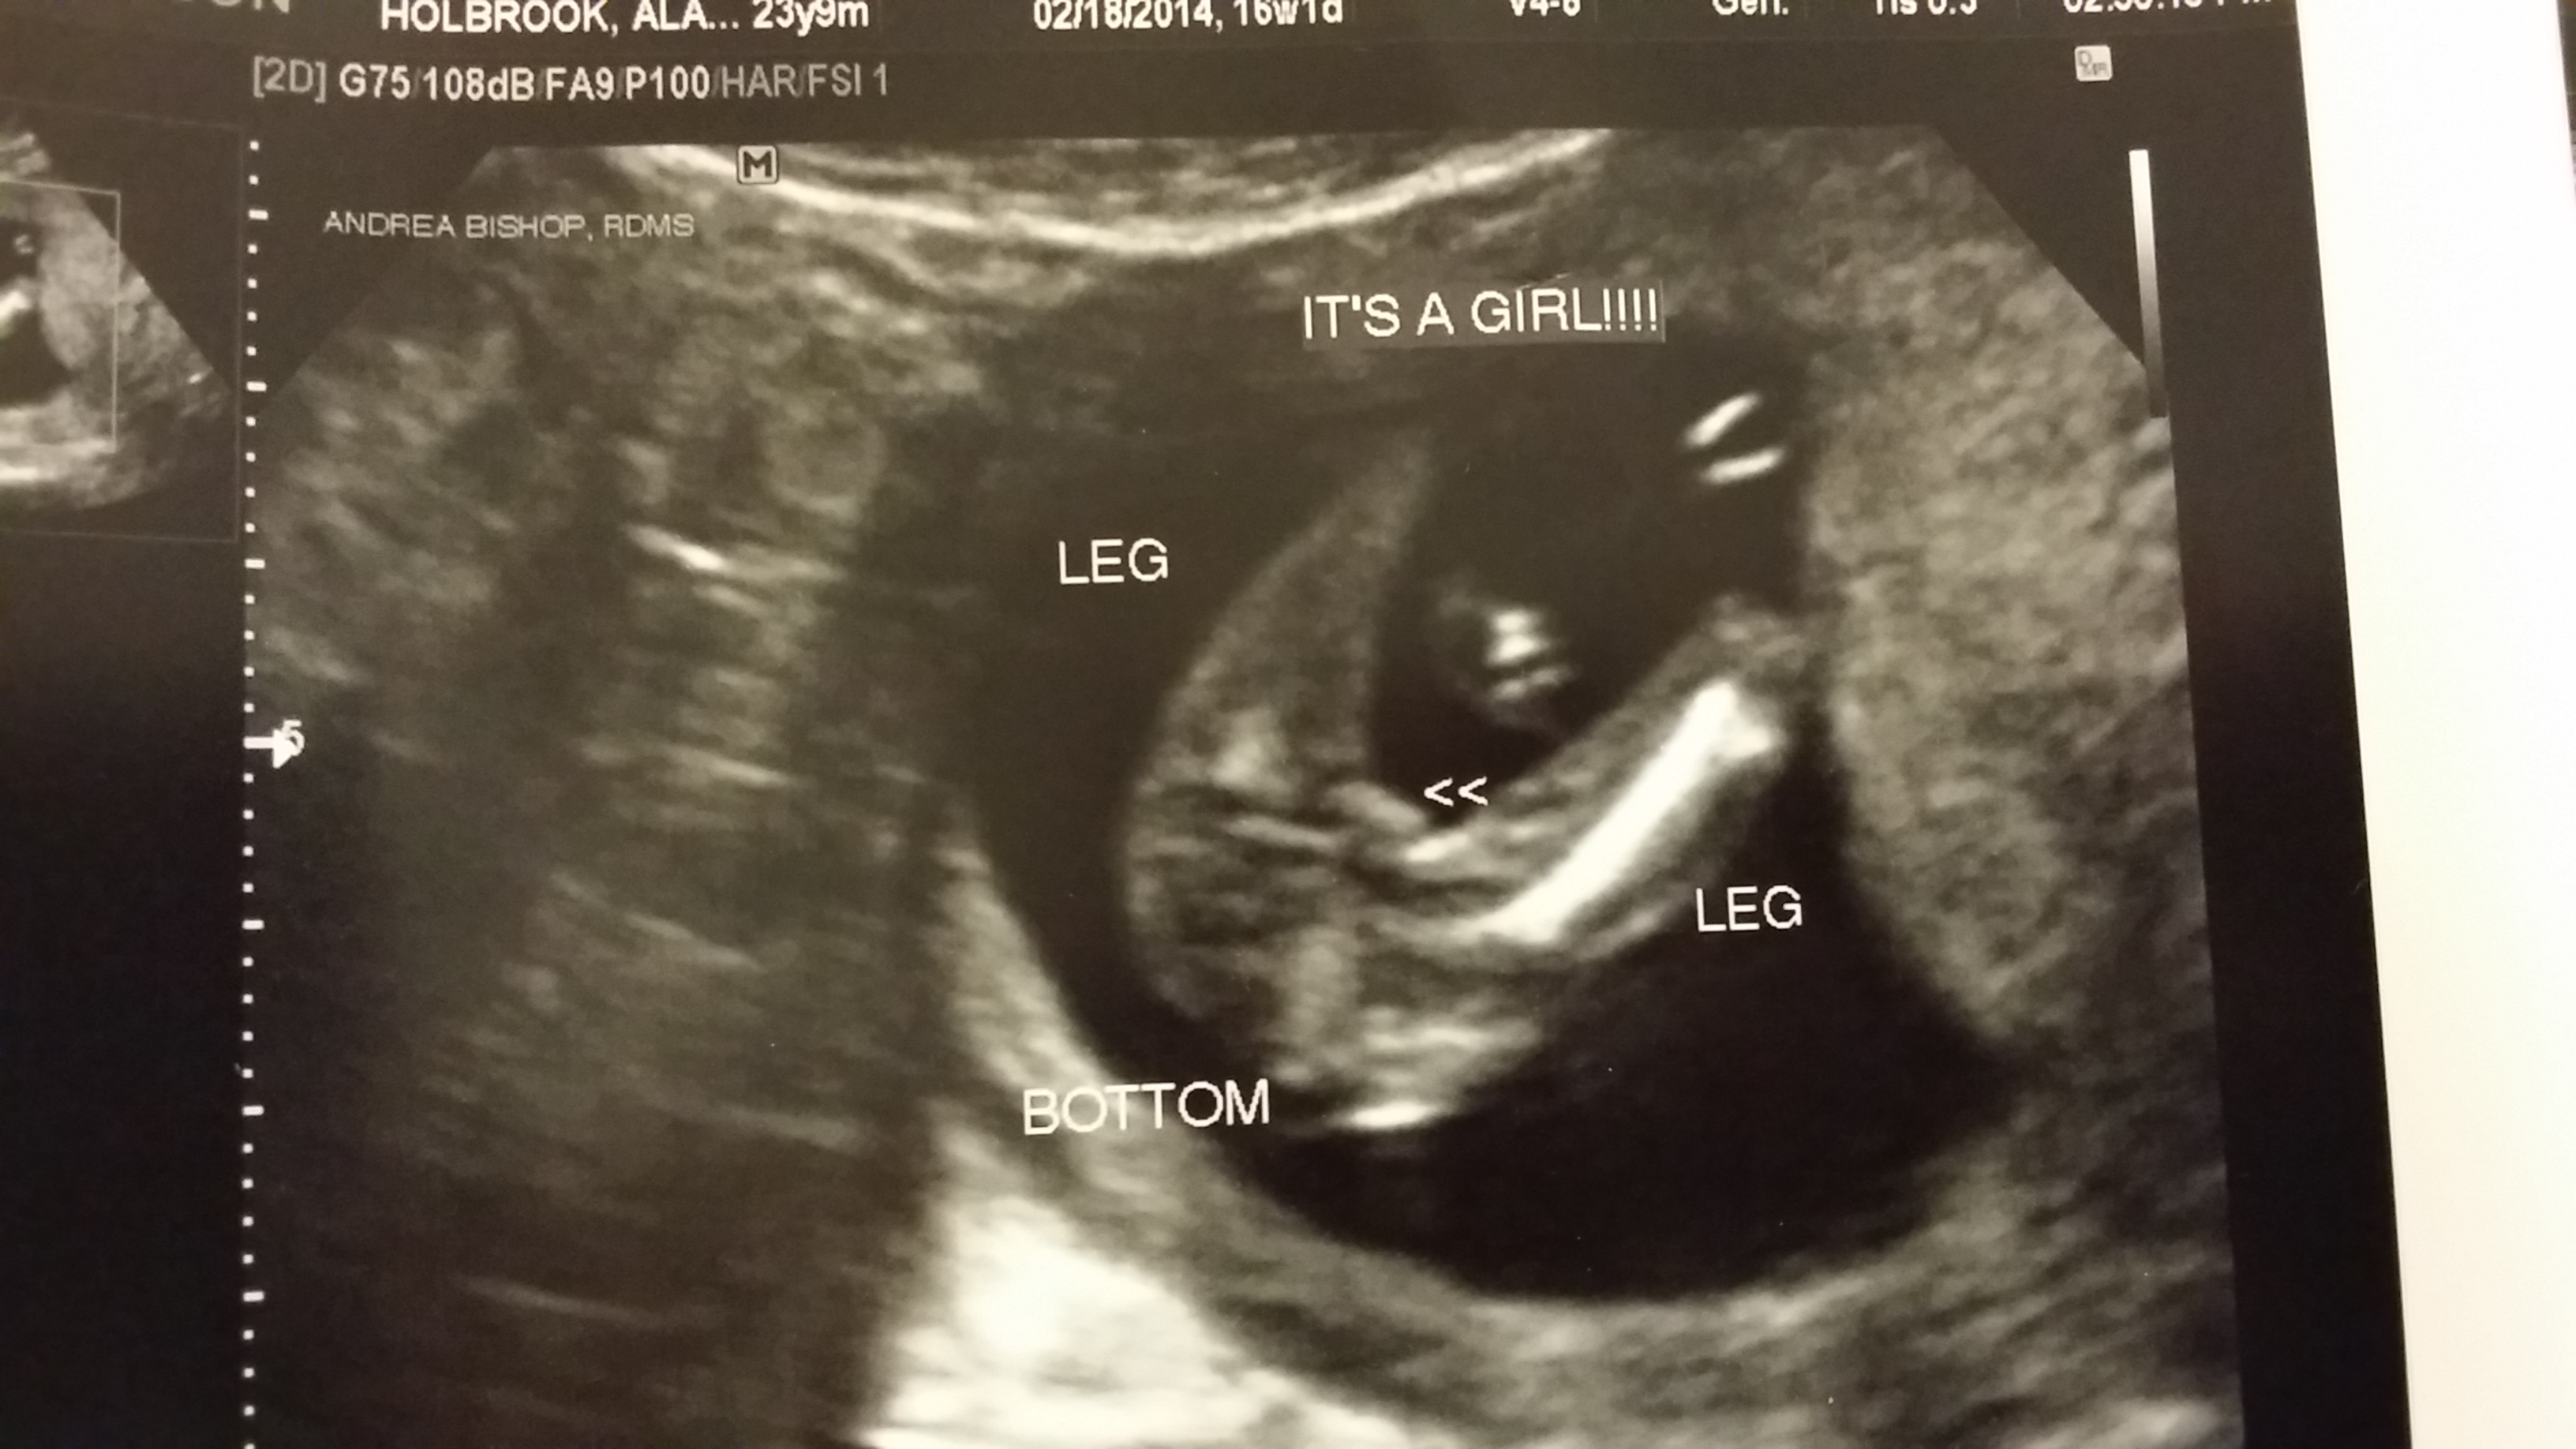

12 week scan potty shot. Sonographer adamant on gender

Had our 12 week ultrasound today!! I just had my 20 week u/s and they said it was a girl. Nub method has very high accuracy when measuring angle of nub compared to spine! He is measuring at 5.5 pounds. I have two boy's, so i'm skeptical. 12 week ultrasound gender ultrasound gender prediction pregnancy gender reveal pregnancy goals pregnancy photos baby photos 12 week scan how to 'predict' baby's gender from an early ultrasound. How our 12 week ultrasound showed baby's gender! You must also remember that a nub analysis before 12 weeks of pregnancy, especially for babygram can give you a reliable prediction of your baby's gender.

My mom bawled her eyes out and you can hear. 11 week ultrasound gender prediction november 2019 birth. Nub method has very high accuracy when measuring angle of nub compared to spine! Predictions made by sonographers during routine obstetric ultrasound. 12 week ultrasound gender ultrasound gender prediction pregnancy gender reveal pregnancy goals pregnancy photos baby photos 12 week scan how to 'predict' baby's gender from an early ultrasound. A theory that really works, here's how to use your scan to predict your baby's gender. 12 week ultrasound gender prediction mp3 & mp4. 19 week gender scan accuracy. Experts at babygram use the nub theory to thoroughly analyze your ultrasound. 12 weeks 5 days ultrasound/ gender reveal. We do this using the nub method! Ultrasound and gender detection gender is determined by visually inspecting the ultrasound several studies have been conducted to determine the accuracy of gender prediction at different at 12 weeks, 99% of male gender predictions were correct, and 91% of female predictions were. You mentioned that you're 12 weeks along.

Whats the accuracy of sonographic determination of fetal gender study. Full text ultrasound measurement learning of fetal sex. Biomedical papers of the medical faculty of the university palacky, olomouc, czech republic (2012) 5. Early baby gender predictor explained 2019. Updated on october 18, 2008. It's the grainy, black and white image that makes it all seem so real and we've found four. Gender confirmed by harmony test! 12 weeks 5 days ultrasound/ gender reveal.